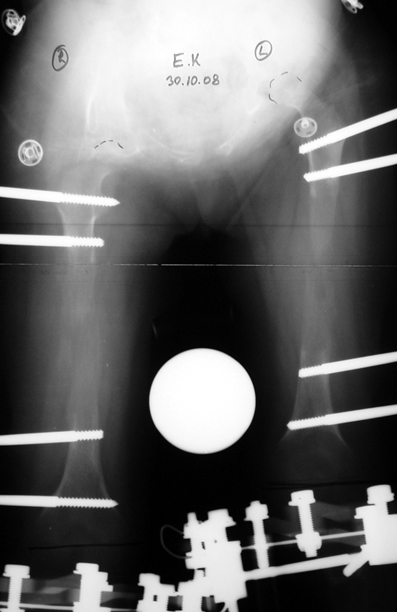

14 ve 16 yaşlar arasında her iki femurda toplam 10-12 cm boy uzatma her iki kalçanın fleksiyon deformitesinin düzeltilmesi (bu lomber hiperlordozu düzeltir) her iki kalçanın varus deformitesini düzeltme ortalama eksternal fiksasyon tedavi süresi = 10-12 ay

12-14 yaşları arasında Her iki tibiada toplam 10-15cm boy uzatma (iki seviyeli uzatma) Proksimal tibianın varus deformitesini proksimal osteotomi ile düzeltilmesi Distal tibianın varus deformitesi distal osteotomi ile düzeltmesi Distal tibianın varus deformitesi distal osteotomi ile düzeltmesi Boy uzatmanın sonunda lateral kollateral ligamentin gerilmesi Ortalama eksternal fiksasyon tedavi süresi = 8-10 ay